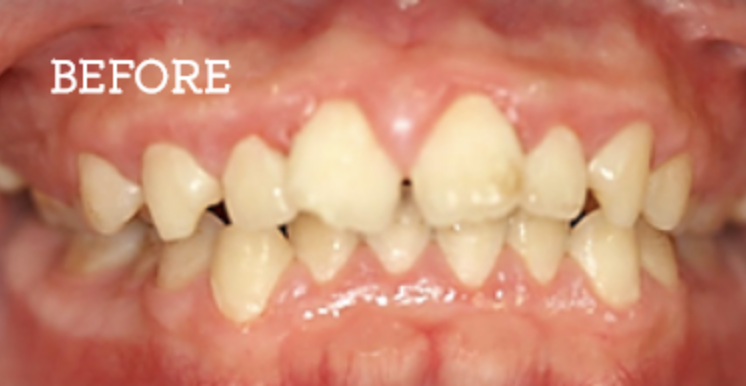

症例

お困りごとを参考に、治療のbefore・afterが確認できます。治療過程や期間、費用などを参考にご覧ください。